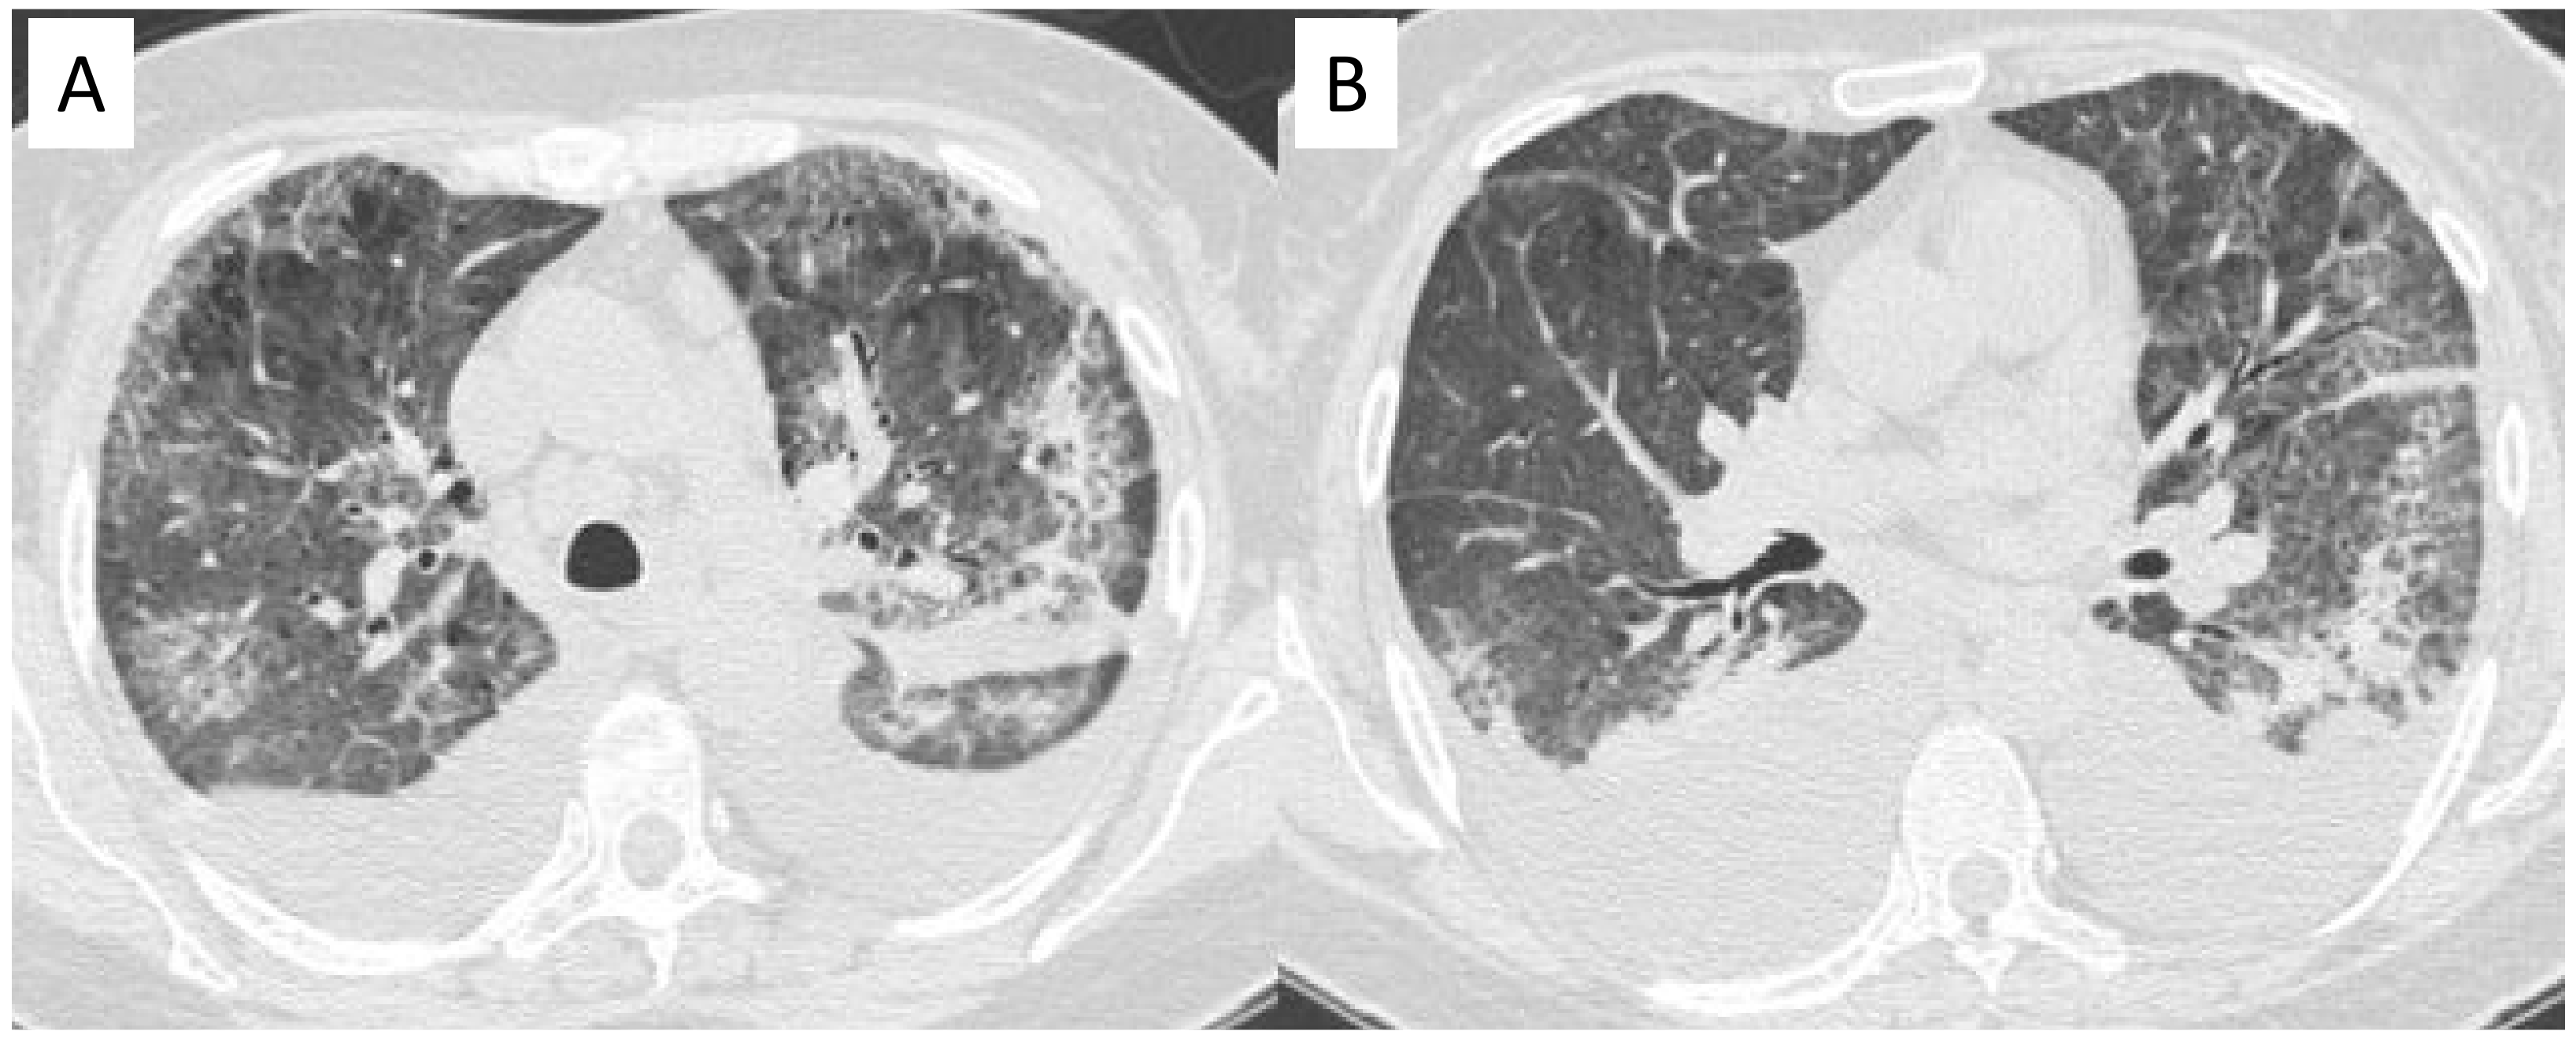

2.3. Microscopic Polyangiitis (MPA)

| MPA | GGOs due to hemorrhagic alveolitis (common); consolidation, nodules with centrilobular distribution (less common) |